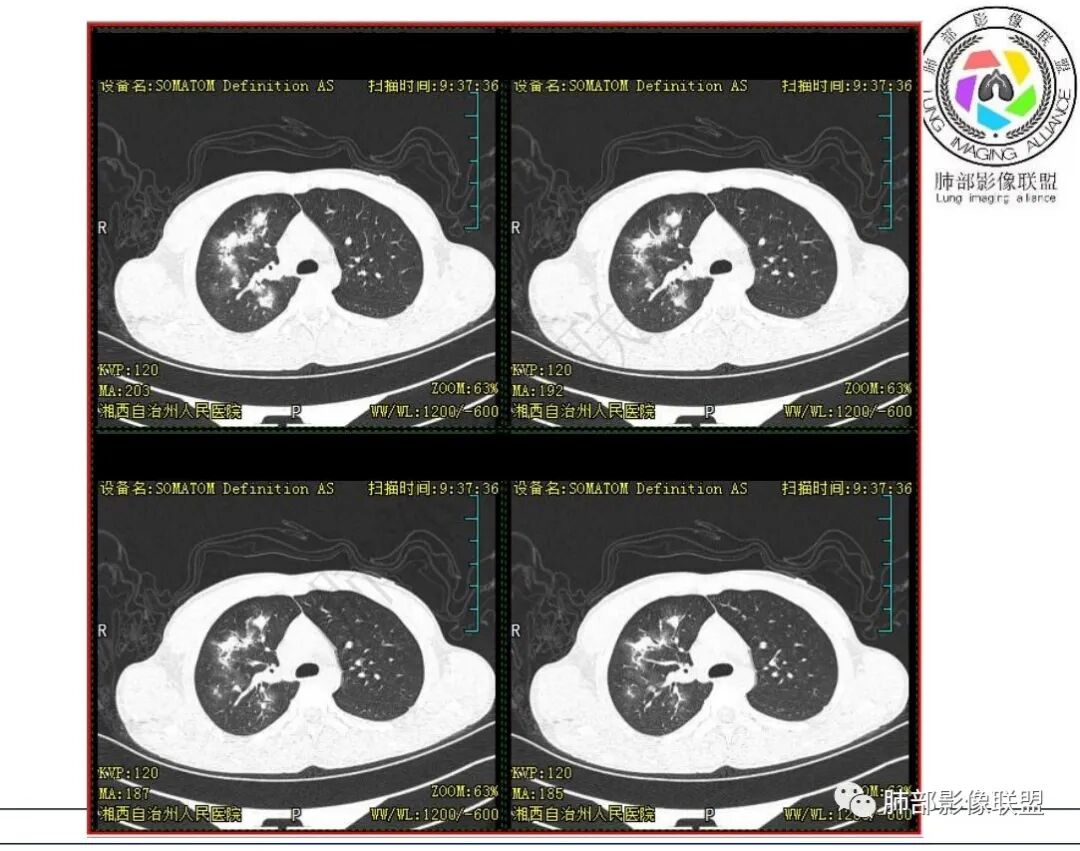

影像:右肺上叶多发实变影结节影,边界模糊,边缘收缩,伴多发空洞,洞壁光滑,部分支气管壁增厚。

3.首次CT提示:右肺上叶多发结节影及实变影,簇状分布,周围散在磨玻璃影,结节内多类圆形空洞,内壁光整,有一定张力,偶见液平。部分支气管壁增厚。

考虑良性感染性病变可能。

4.患者年龄、临床与影像都会首先考虑结核,但是结核相关各项实验室检查均阴性,没有找到病原学依据。

因此,还应当排除NTM,影像可以酷似结核灶。